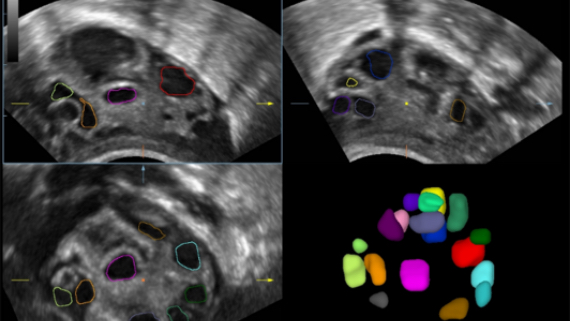

DE11-3E Dual-Volume Solution

DE11-3E Dual-Volume Solution

Images cliniques